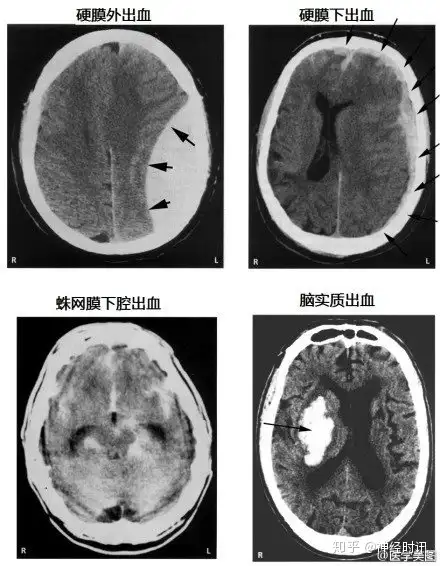

几种常见致死性脑病的CT表现

各种颅内出血

几种类型脑出血的CT表现